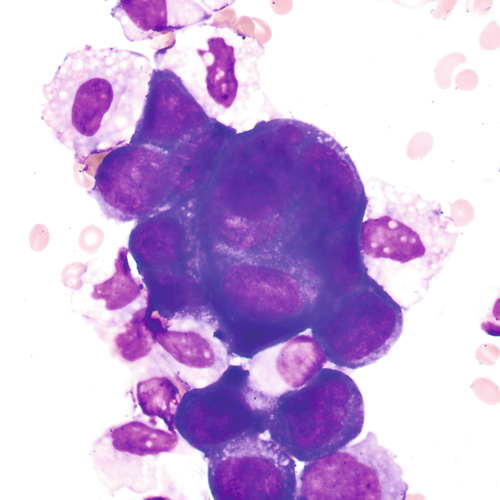

Macrophage with engulfed RBCs. RBCs are digested by enzymatic activity within the macrophage. The digestive process causes the RBCs to lose color and to appear as vacuoles within the cytoplasm of some macrophages.

Large cells with eccentric nuclei and vacuolated cytoplasm may be present in all body fluids. They may be seen with or without inclusions, such as RBCs, siderotic granules, or lipids.